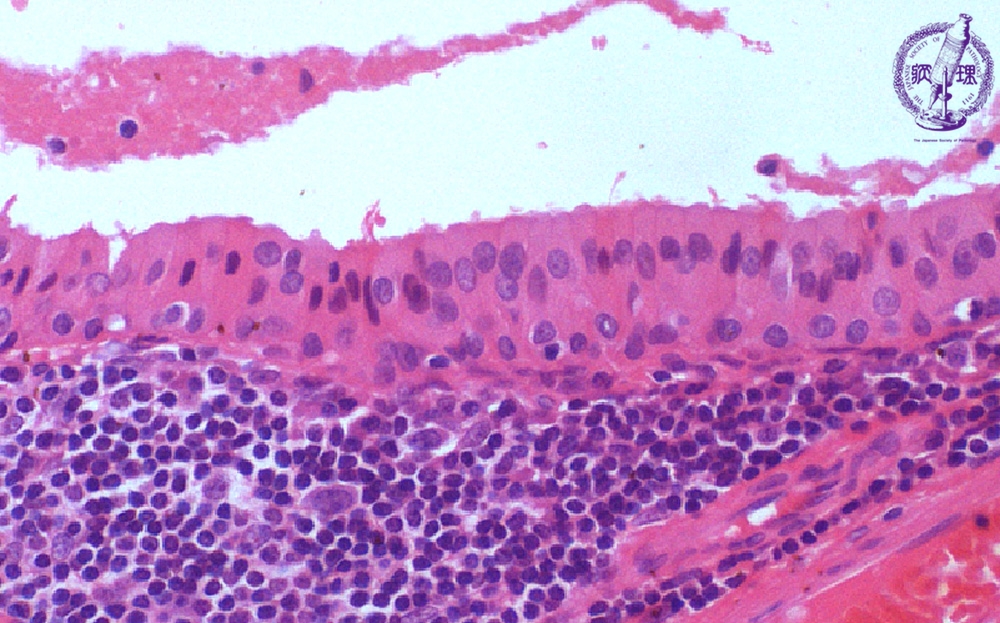

Microscopic finding (HE stain, high-power view):The tumor cells lining the cyst are oncocytic due to cytoplasmic eosinophilic granules. These cells have a dual-layered arrangement with inner tall columnar cells and outer cuboidal cells. The stroma (area below the dotted line) is composed of lymphoid tissue.